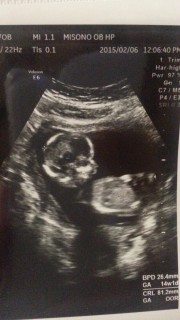

初めての経腹エコーでした! 今までは心臓しか動いてるのが見られなかったけど、 今回はよく動き回っていてとっても可愛かったです。 4DのDVDをもらって主人にみせたところ 「いいなぁ俺も心音聴きたいし健診ついていきたい!!」 と言っていました(^◇^)

初めて旦那も一緒に産婦人科へ(*^o^*) 緊張してたのかガチガチ!笑 べびたんはしゃっくり連発しながら 足を曲げたり伸ばしたり(*^^*) 心臓もちゃんと動いてたし 問題も無さそうだったので ひとまず安心(*^^)v 次は3週間後(^O^) 性別分かるかな?笑 次回が楽しみ♪